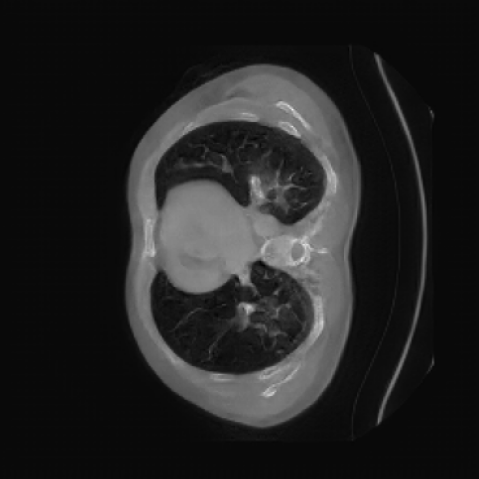

The motivation for this work arises from the need to address these limitations in the synthesis of 3D medical images. Current techniques do not produce high-resolution 3D images that preserve spatial coherence and capture the full complexity of medical data, as shown in Figure 2, 5. The development of advanced 3D generative models tailored specifically for medical imaging could not only improve the quality of synthetic medical images but also help alleviate data scarcity, enhance privacy protection, reduce computational requirement and ultimately advance the use of deep learning in healthcare applications.

As shown in Figure 5, the generated slices exhibit high consistency across adjacent slices. The anatomical structures and semantic patterns are smoothly and coherently preserved between slices, indicating that our model is capable of generating 3D-consistent synthetic images rather than isolated 2D slices.